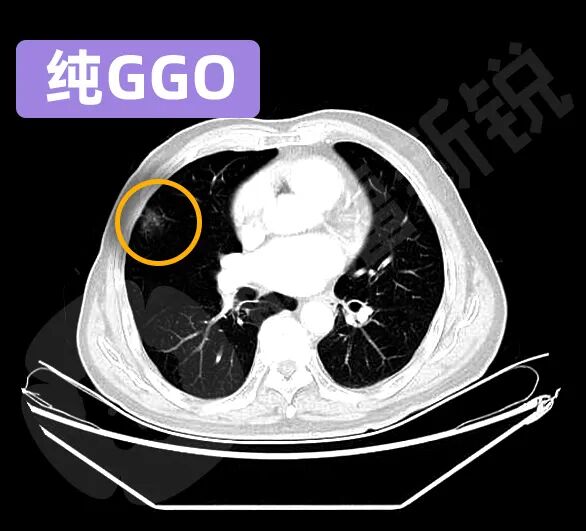

根据磨玻璃结节所包含的实性成分的不同,又可以分为纯GGO、混杂GGO、半实性GGO等不同亚型。

纯GGO在影像上显示为云雾状,就像冬天在玻璃上哈了一口气的效果。